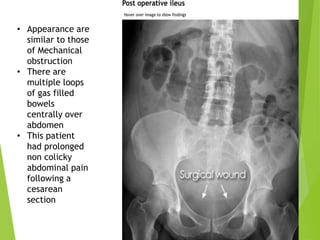

ILEUS

Hypomotility of the gastrointestinal tract in the

absence of mechanical bowel obstruction.

• Appearance are

similar to those

of Mechanical

obstruction

• There are

multiple loops

of gas filled

bowels

centrally over

abdomen

• This patient

had prolonged

non colicky

abdominal pain

following a

cesarean

section